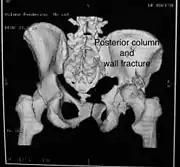

Posterior column and wall fracture as seen on 3D CT

| Posterior column | As with posterior wall injury, this also typically occurs due to dash board injury. | Posterior column + Posterior wall | These fractures are extension of elementary fractures. With involvement of posterior wall, the difficulty in treatment increases. These fractures are rarely amenable to non-surgical treatment. Due to posterior wall fracture, the hip is usually dislocated posteriorly, requiring immediate reduction of dislocation and surgical reconstruction after few days.

Posterior column with posterior wall fracture occurs due to dash board injury. Antero posterior view may give clue to these injuries, Judet views and CT scan help in knowing the extent of injury. |